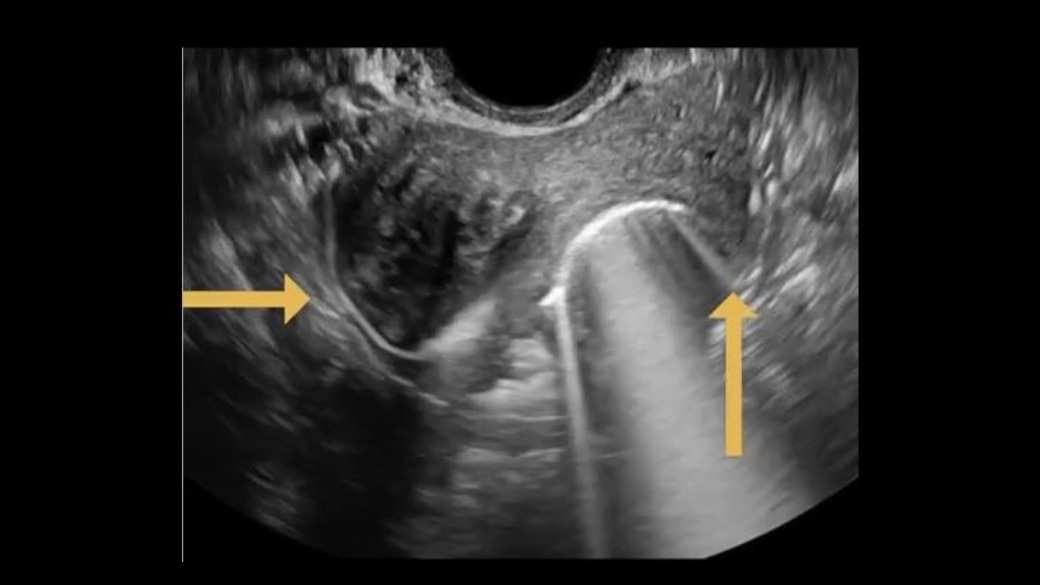

Localize fallopian tubes and visualize tube abnormalities with HyFoSy using ExEm® Foam

ExEm® Foam is an FDA-approved ultrasound contrast agent that allows for convenient in-office ultrasound tubal patency testing for woman with known or suspected infertility.

The HyFoSy procedure using ExEm® Foam allows to inspect the fallopian tubes and its relation to other pelvic organs/structures. It also provides extra details for the assessment of the patient's sub-fertile situation. It is performed by a qualified sonographer and is technically an ultrasound examination that quickly helps to localize fallopian tubes and visualize tube abnormalities.